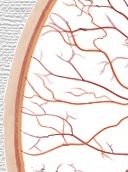

Mácula |

Nervio

óptico |

Retina |

Esclerótida

|

Coroides |

a.

retinal temporal superior |

v.

arteriola

macular superior |

vénula

retinal temporal inferior |

retinal nasal inferior |

retinal nasal superior |